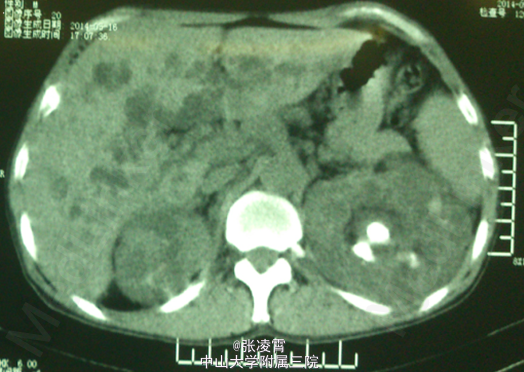

患者男性,51岁,因“左侧腰部胀痛不适20天余”入院。患者20余天前无明显诱因出现左侧腰部胀痛,未伴有发热,寒战,恶心,呕吐,轻度尿频,尿急,尿痛等不适,至柳州市工人医院就诊,尿蛋白+2g/L,潜血阳性,WBC(++),血红蛋白69g/L,肌酐450umol/L;KUB示双肾多发结石,双肾ECT示左肾GFR21.09ml/min,右肾8.84ml/min,考虑为双肾多发结石伴左肾及肾周感染,慢性肾功能不全,尿路感染,肾性贫血,经抗炎等对症治疗后,症状有所缓解。 实验室检查:尿常规:白细胞计数98http://www.medlinker.net/m/casem/12628336计数12.3个/μL,血常规:血红蛋白计数:64g/L。血生化:碳酸氢盐12.0mmol/L,肌酐443μmol/L。凝血四项未见明显异常。 影像学检查:KUB示:双肾多发结石,左侧为著,部分为铸型结石(图1)。外院CTU示:多囊肾,多囊肝,双肾结石(图2、3)。